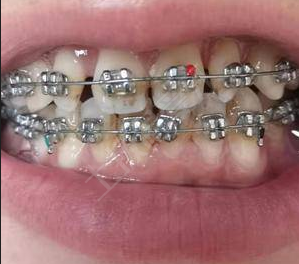

牙齒矯正一般是不能拔門牙的,會(huì)影響牙齒的美觀。具體的要根據(jù)自身牙齒的情況來(lái)決定,如果牙齒出現(xiàn)了損傷,需要把門牙拔出,再通過(guò)矯正牙齒的方法來(lái)改善,可以選擇佩戴隱形牙套,在矯正期間不會(huì)影響整體的美觀,是透明的材質(zhì),矯正后能使牙齒更加的整齊?;謴?fù)期間要定期到醫(yī)院做復(fù)查,要注意口腔的清潔衛(wèi)生。